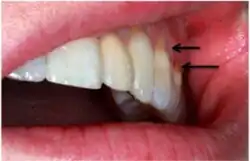

Non-carious cervical lesions on an incisor belonging to Australopithecus africanus. Arrows show the location of the lesions.

Non-carious cervical lesions (NCCLs) are a group of lesions that are characterised by a loss of hard dental tissue at the cementoenamel junction (CEJ) region at the neck of the tooth, without the action of microorganisms or inflammatory processes.[1] These lesions vary in shape from regular depressions that look like a dome or a cup, to deep wedge-shaped defects with the apex pointing inwards.[1] NCCLs can occur either above or below the level of the gum, at any of the surfaces of the teeth.

An example of non-carious cervical lesions.